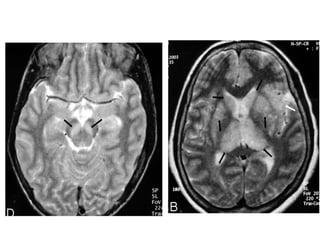

NEUROIMAGING

(A) CT scan showing thalamic hypodensity (B) MRI scan showing hyperintense thalami

(A) CT scanshowing thalamic hypodensity (B) MRI scan showing hyperintense thalami

• #23 xial T2-weighted image shows bilateral thalamic and basal ganglia lesions (black arrows). Note left-sided insular involvement (white arrow).